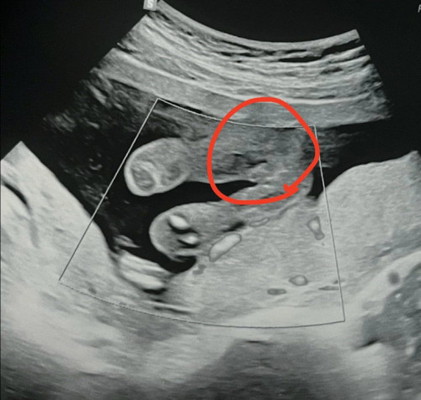

มองเป็นเพศอะไรกันคะหมอบอกอาจจะผู้หญิง เเต่เเม่กับพ่อมองเป็นผู้ชายเหมือนไข่กับจู๋ รอไปซาวด์คลินิคดูอีกทีเดือนหน้าค่ะ

ถ้าอายุ 20++ w มีจุ๊ดจู๋ แต่ยังไม่มีอัณฑะ เพราะยังไม่ห้อยลงมาค่ะ ผู้ชายพัฒนาเครื่องเพศช้ากว่าผู้หญิง รอเดือนหน้าน่าจะชัวร์ค่ะ